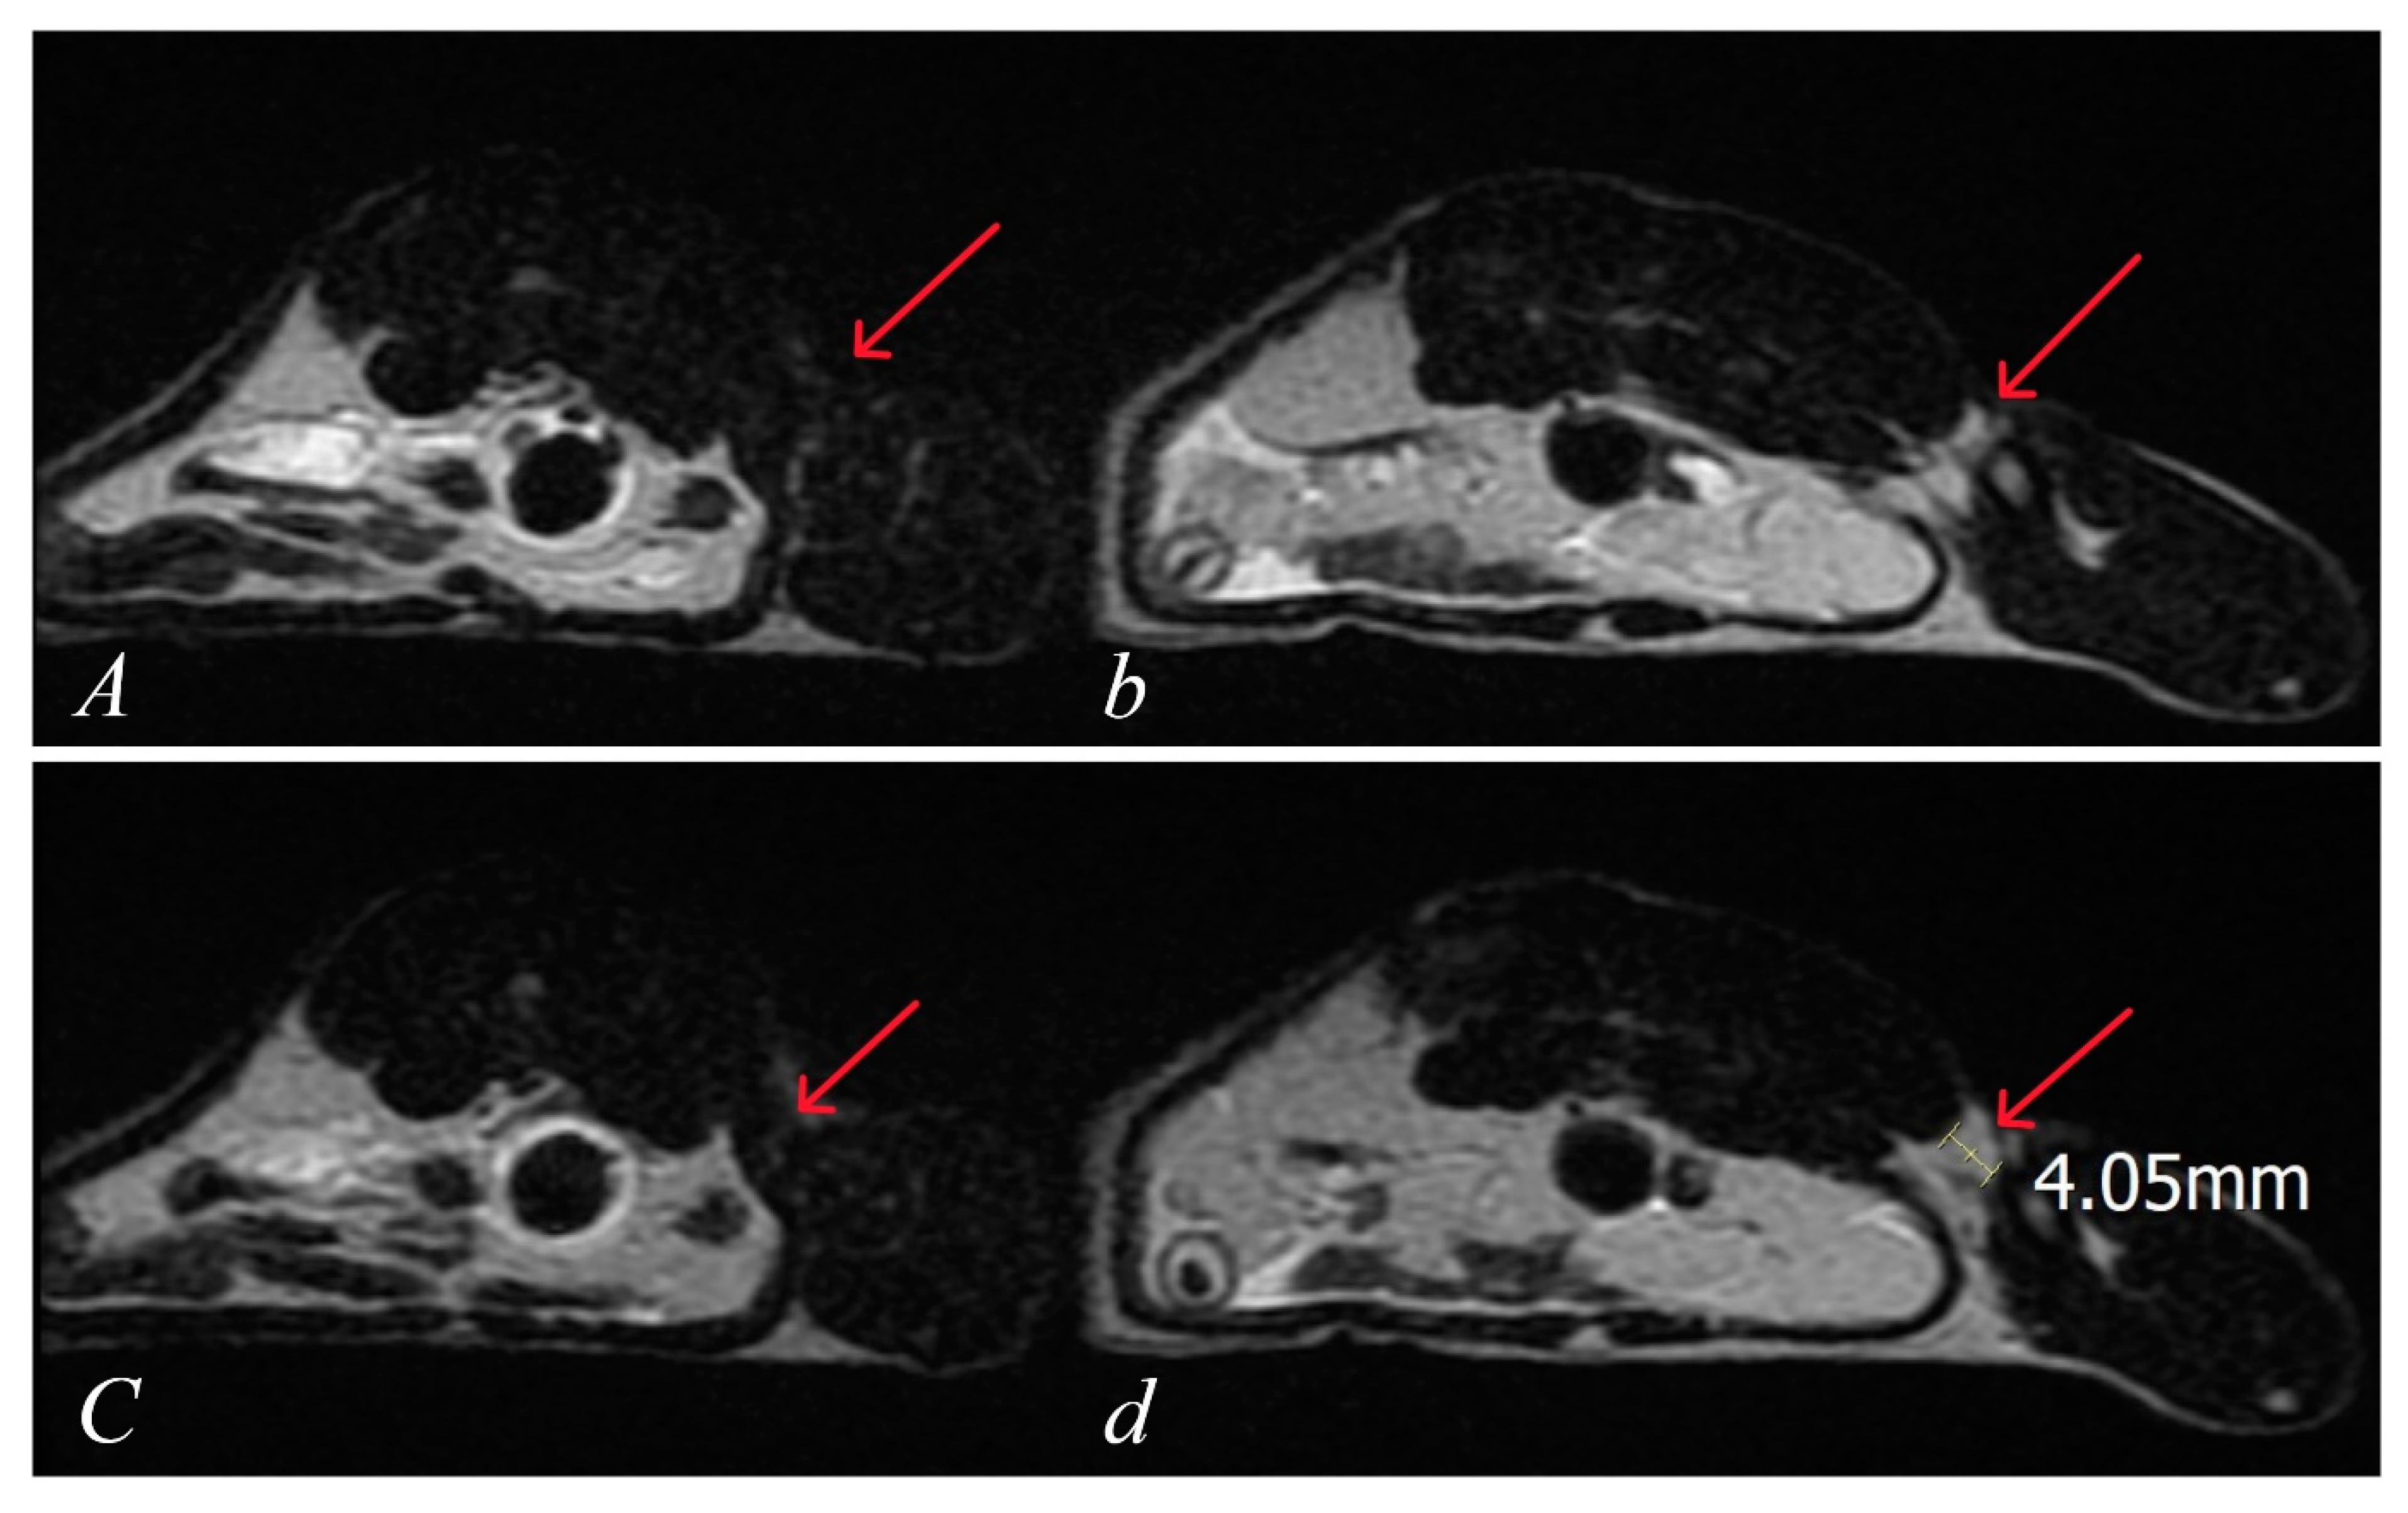

2.5.5. MRI Imaging and Measurements